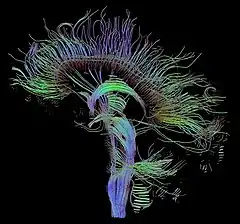

Biology data visualization is a branch of bioinformatics concerned with the application of computer graphics, scientific visualization, and information visualization to different areas of the life sciences. This includes visualization of sequences, genomes, alignments, phylogenies, macromolecular structures, systems biology, microscopy, and magnetic resonance imaging data. Software tools used for visualizing biological data range from simple, standalone programs to complex, integrated systems.

An emerging trend is the blurring of boundaries between the visualization of 3D structures at atomic resolution, visualization of larger complexes by cryo-electron microscopy, and visualization of the location of proteins and complexes within whole cells and tissues.[1][2]

A second emerging trend is an increase in the availability and importance of time-resolved data from systems biology, electron microscopy[3][4] and cell and tissue imaging. In contrast, visualization of trajectories has long been a prominent part of molecular dynamics.

Finally, as datasets are increasing in size, complexity, and interconnectedness, biological visualization systems are improving in usability, data integration and standardization.